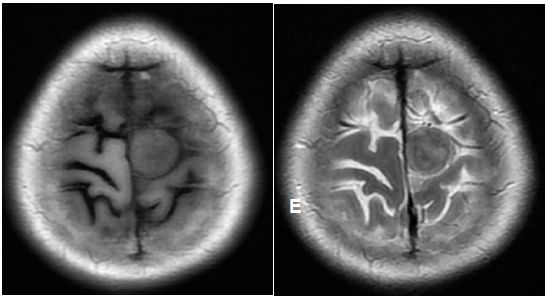

入院后完善相关检查,头颅磁共振检查示:左侧顶部矢状窦旁等T1等长T2为主混杂信号类圆形影,大小约16mm×17mm,外周见T2低信号环及脑实质水肿带,增强后周围呈明显不均匀环形强化(图1)

图1. 左侧顶部矢状窦旁等T1等长T2为主混杂信号类圆形影,大小约16mm×17mm,外周见T2低信号环及脑实质水肿带,增强后周围呈明显不均匀环形强化。脑室、脑池和脑沟未见扩大,中线结构无移位。首先考虑脑膜起源或累及脑膜肿瘤。